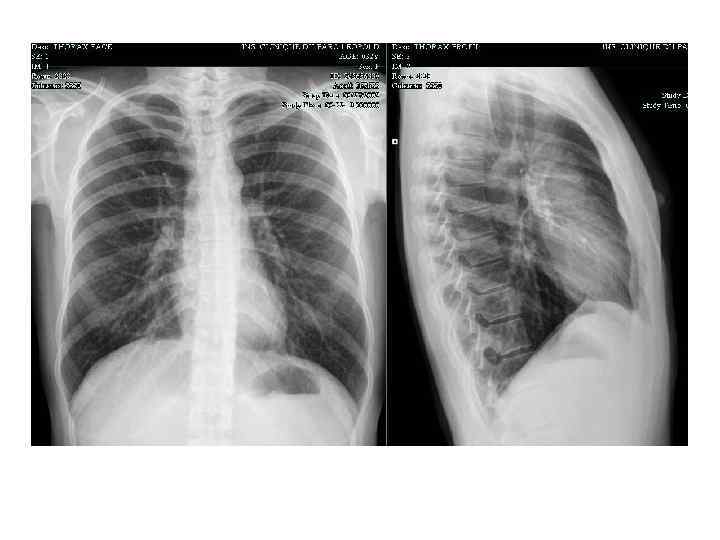

Рентгеновское изображение. • • Легочные поля Корень легкого Купол плевры Синусы плевры Ребра Ключица Тень сердца диафрагма